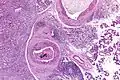

Low magnification micrograph of a salivary duct carcinoma with characteristic comedonecrosis (left of image) adjacent to normal parotid gland (right of image). H&E stain.

Salivary duct carcinoma (SDC) is a rare type of aggressive cancer that arises from the salivary glands.[1] It is predominantly seen in men and, generally, has a poor prognosis.[2] Other high grade carcinomas can mimic SDC. About 40-60% of SDC arise in pleomorphic adenomas.[3] Most, if not all, SDCs express androgen receptor by immunohistochemistry.[4] Therapeutically relevant genetic alterations include ERBB2/Her2 amplification, PIK3CA and/or HRAS mutations.[5][6]

Their histologic appearance is similar to ductal breast carcinoma.